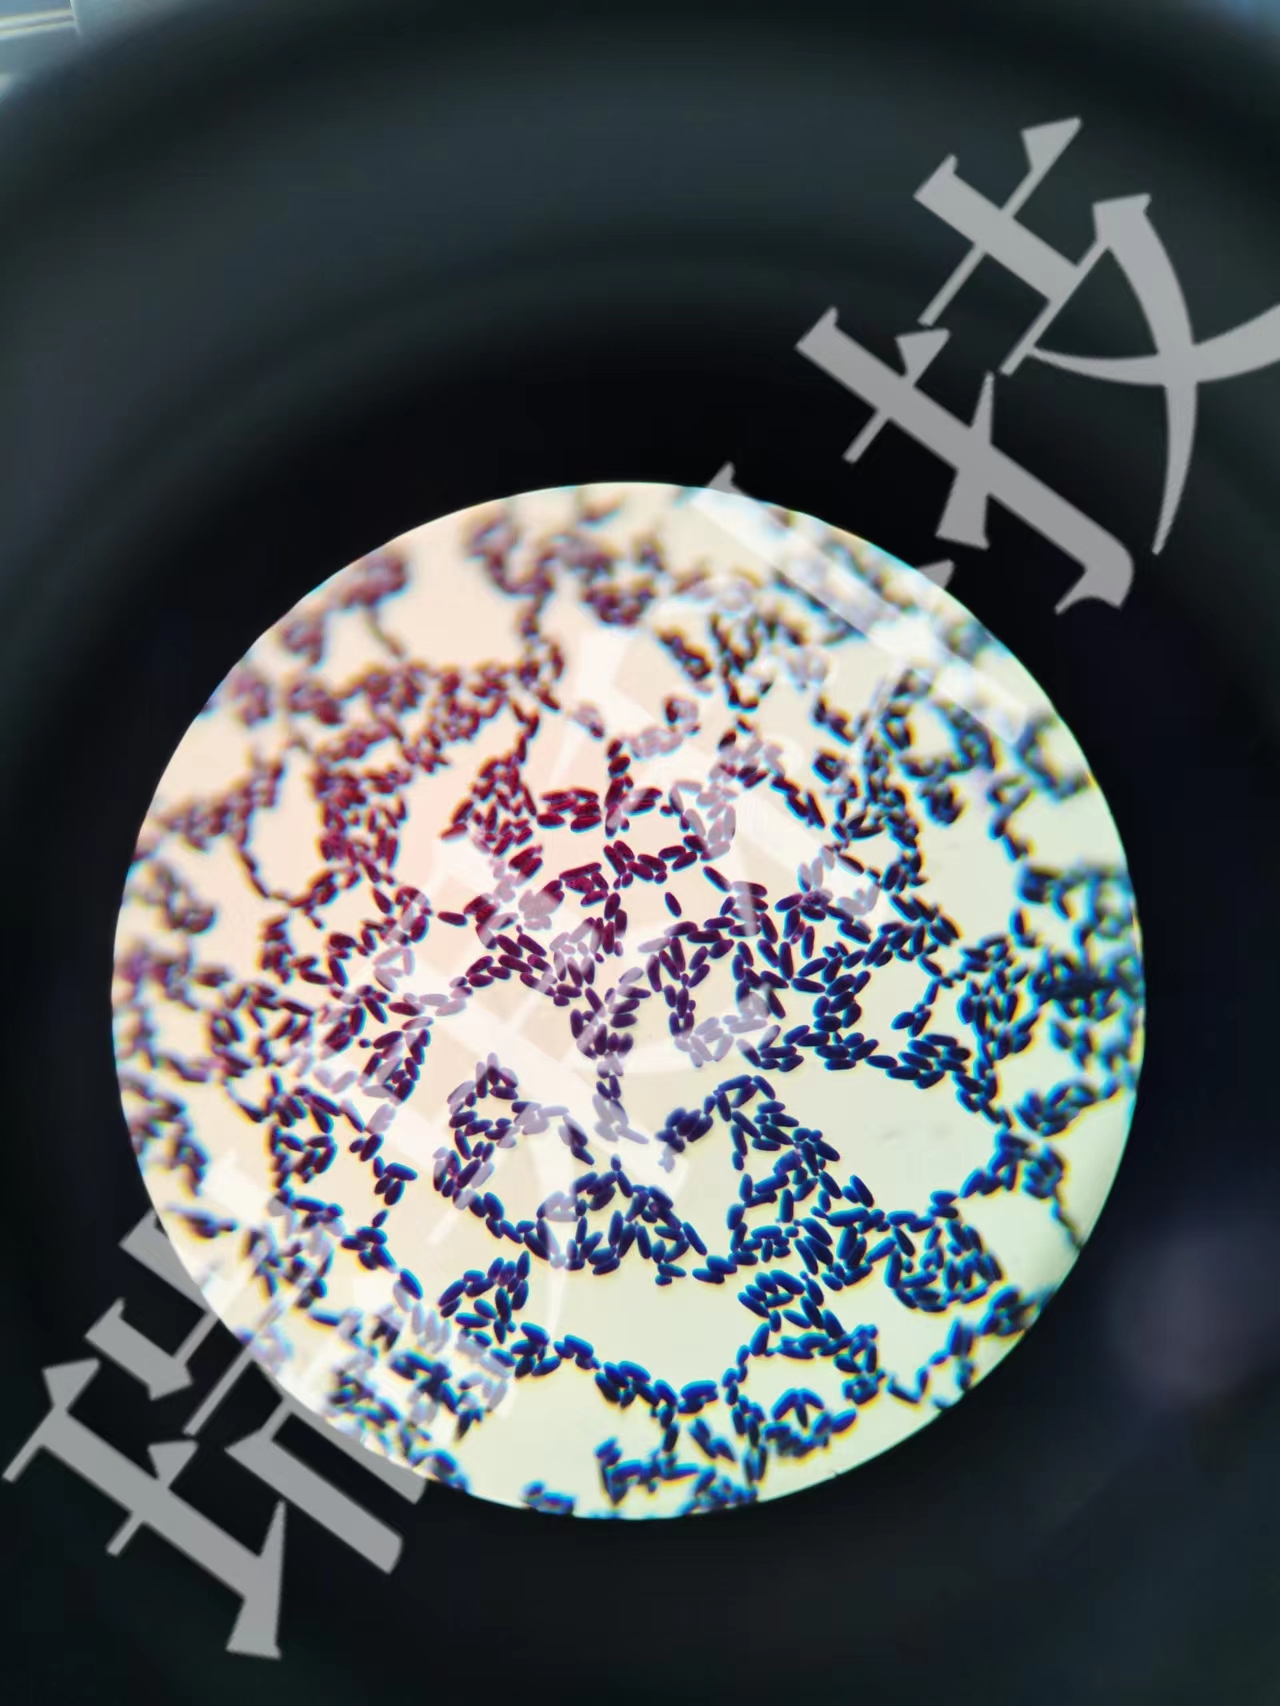

美國(guó)國(guó)家癌癥研究所的Maria Teresa Landi和同事測(cè)序了232名過(guò)去從未吸煙的肺癌患者(平均診斷年齡64.8歲,75.4%為女性),嘗試識(shí)別出非吸煙者所患癌癥特有的遺傳模式?;诨蚪M變異,這些腫瘤可大概分成三類,而且一些進(jìn)展快速,另一些則進(jìn)展緩慢。區(qū)分這些亞型的特征包括低突變負(fù)荷的高瘤內(nèi)異質(zhì)性、特定染色體改變加EGFR基因高頻變異,以及全基因組折疊。研究人員表示,患有肺癌的吸煙者患上這三種亞型的頻率不同,可為精準(zhǔn)醫(yī)療提供參考。